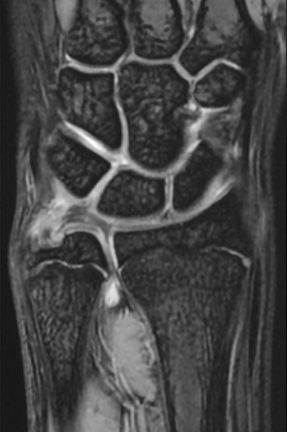

単純X線の他、MRI、手関節造影/CTを行います。単純X線では、TFCC自体は映りません。しかし、骨形態の評価、とくに突き上げ症候群の評価に有用であり、必須の検査の1つです。MRIではTFCCの損傷の有無を評価します。また、ECU腱鞘炎などその他の障害/疾患の有無を確認します。しかしながら、MRIではTFCCの詳細な評価が難しい場合があり、手関節造影/CTが必要となることがあります。手関節造影/CTでは、造影剤を橈骨手根関節内および遠位橈尺関節内に注入しTFCCの円盤部や末梢部、表層部、および小窩(Fovea)部などでの断裂形態を確認します。その他、手根骨間靱帯損傷や手関節尺側部の骨形態について評価します。

【MRI】